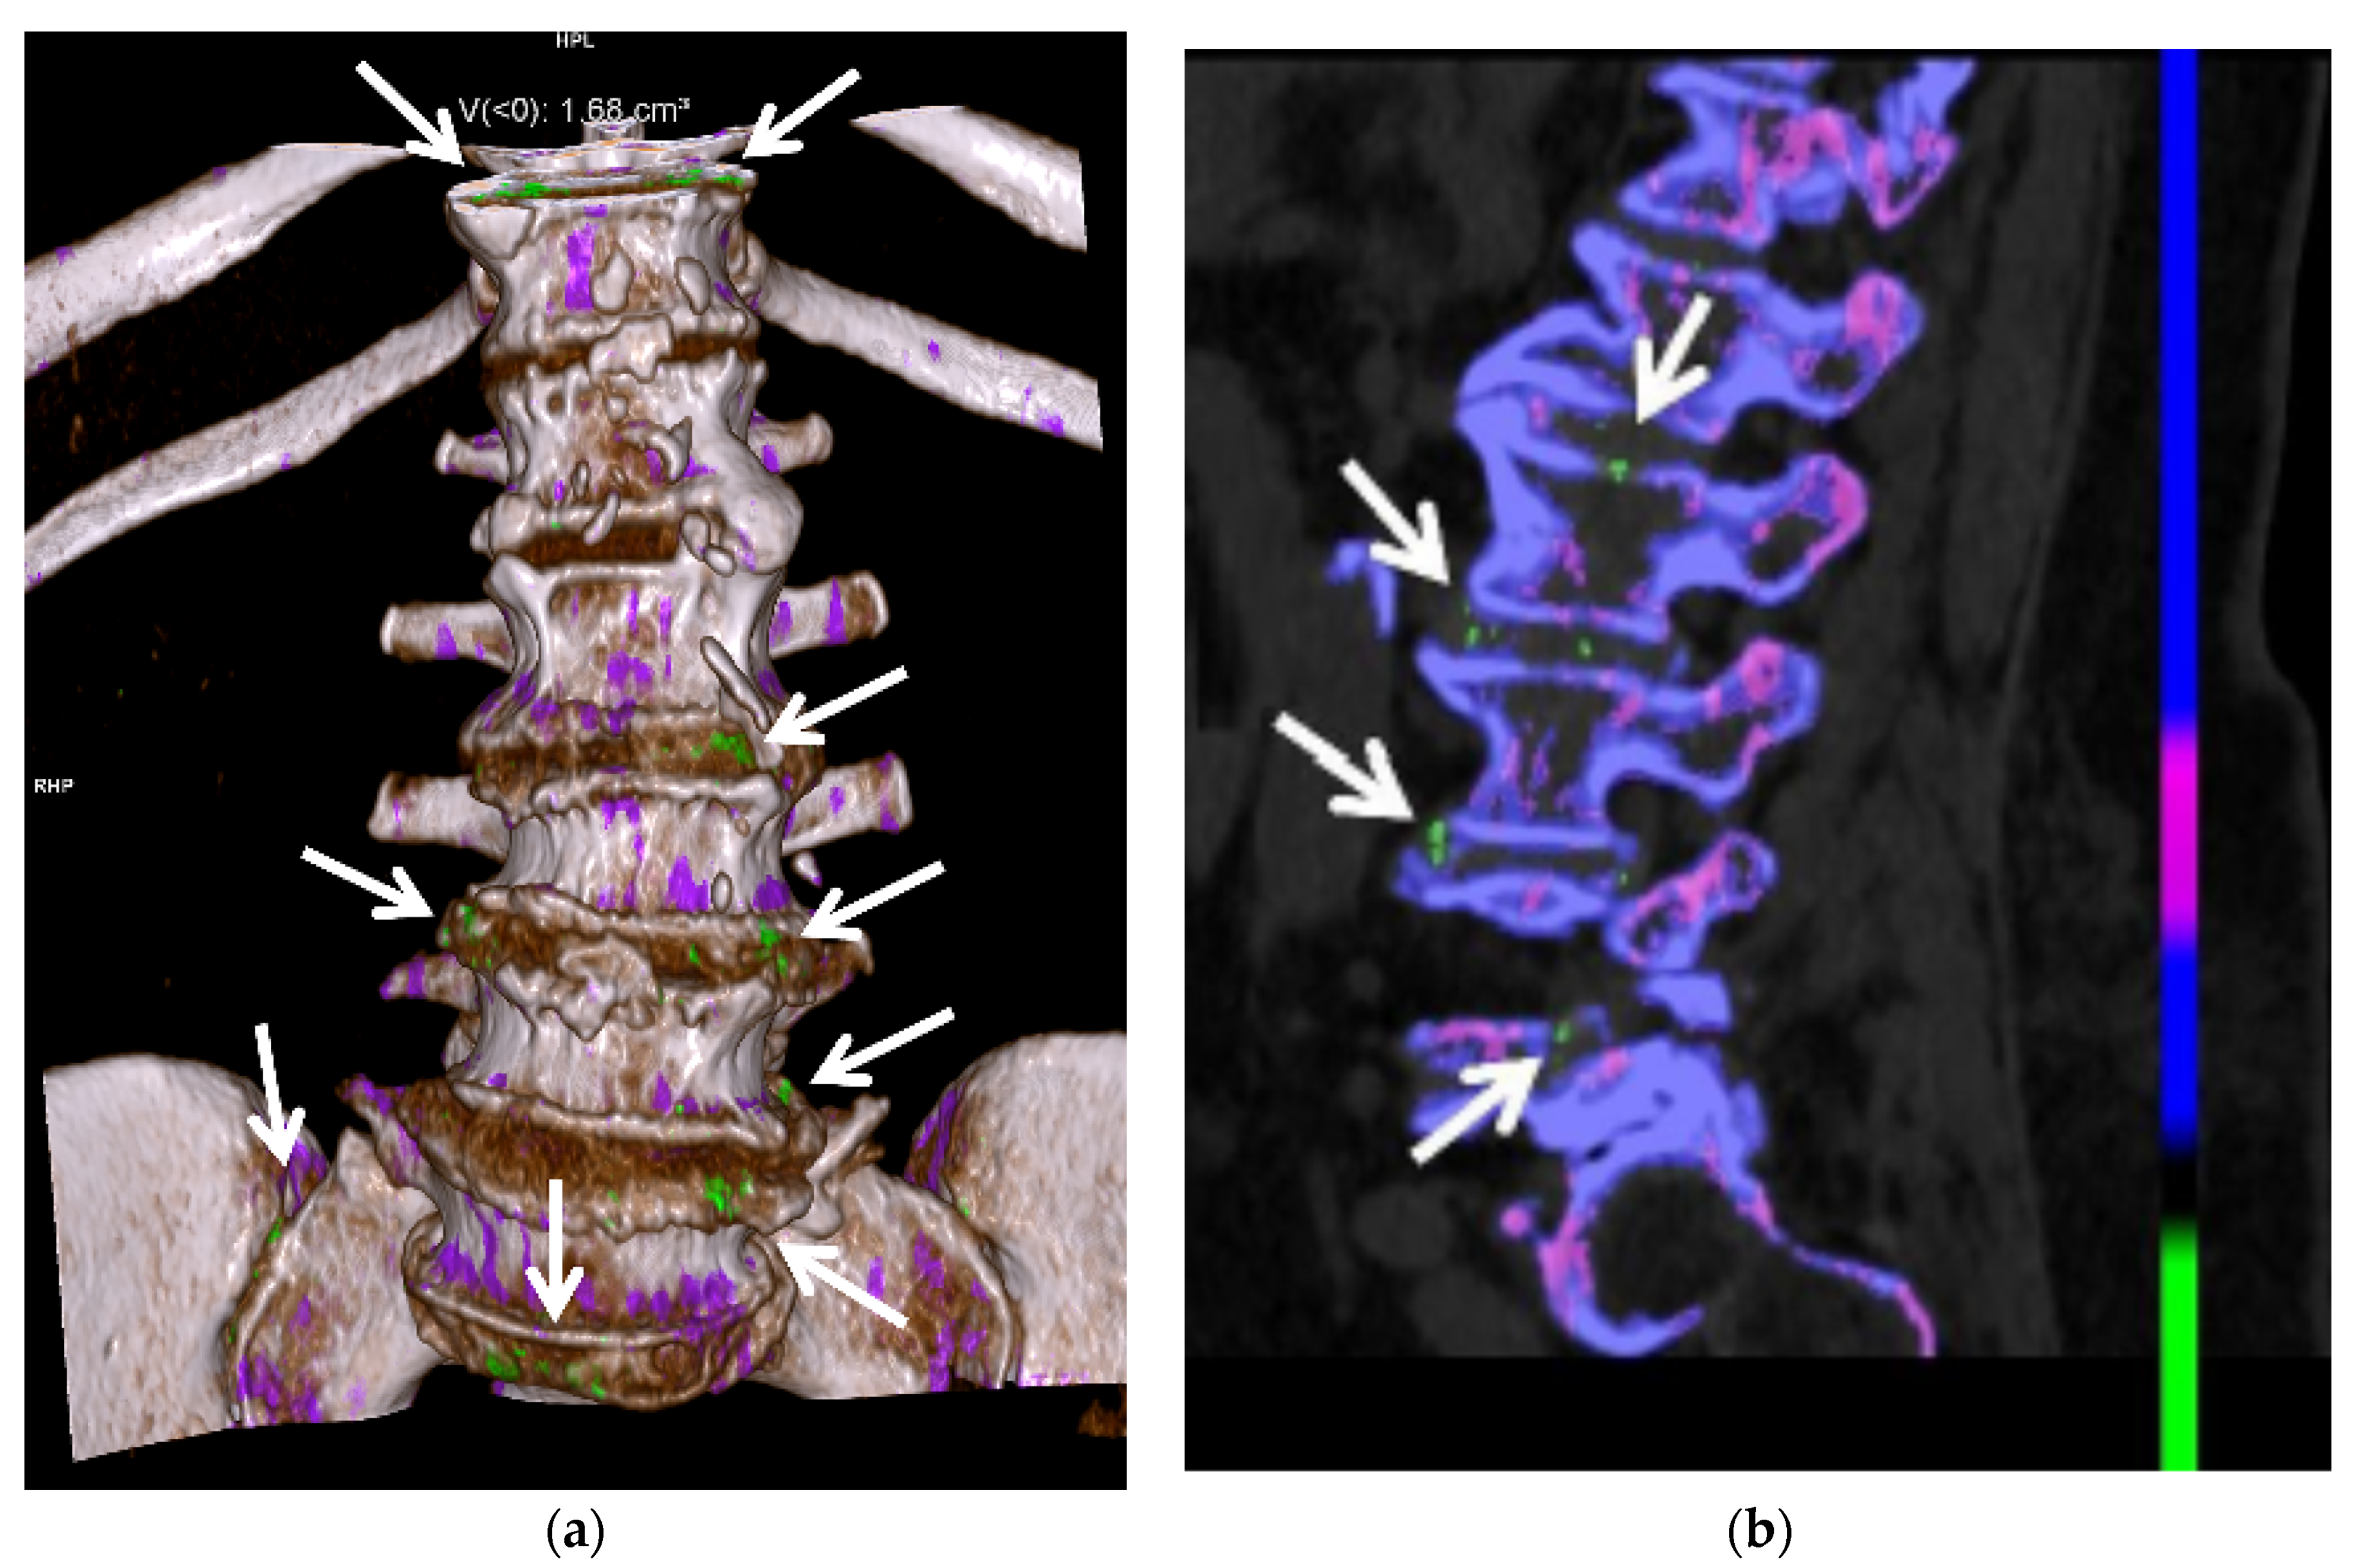

3.3. Computed Tomography (CT): Conventional and Dual Energy (DECT)